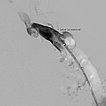

The last remaining open vascular channels of the venous malformation are now further treated with ethanol gel in an additional sclerotherapy session. The image shows a phlebography using the direct puncture technique. Ethanol gel as the sclerosing agent is particularly effective and, due to its high viscosity, less in danger of leaking into the deep conducting venous system via remaining connections or draining veins.

Injection of the ethanol gel (not radiopaque) results in displacement of the contrast agent by the gel.